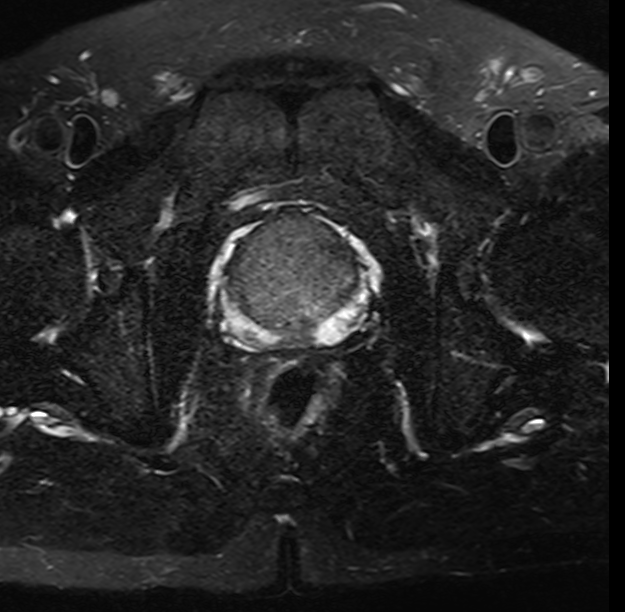

70歲的患者林大伯,揭西人,因反複的尿頻、尿急及排尿困難要求手術治療收住院。經前列腺特異抗原篩查、前列腺MRI增強掃描,考慮前列腺癌。後經前列腺穿刺活檢術,确診爲高分化前列腺癌。

△前列腺MRI增強掃描